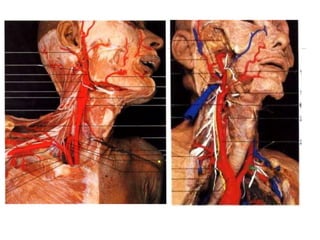

• A ACI se origina da ACC no nível C3-C4 ou C4-C5.

• Inicialmente possui dois segmentos, o bulbo carotídeo

e o segmento cervical (C1).

• Situa-se medialmente à ACE a medida que ascende no

pescoço, embora origina-se lateralmente a esta; é

anterior e mediamente a VJI.

• Não apresenta ramos cervicais.